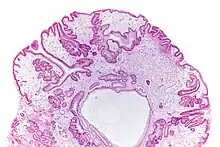

| Micrograph of a gastric juvenile polyp, as may be seen in juvenile polyposis syndrome. H&E stain | |